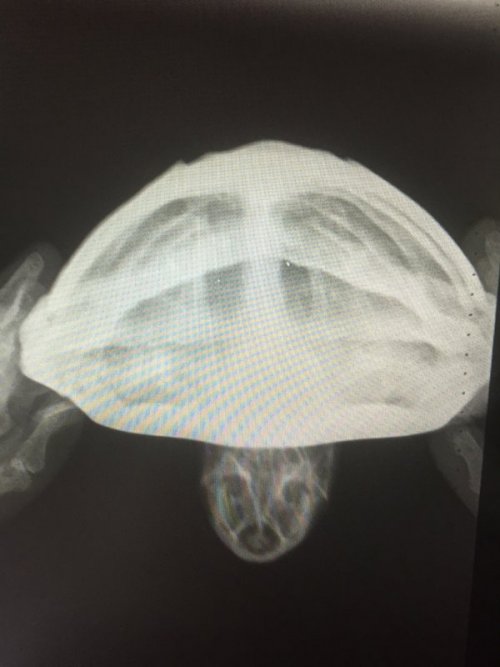

Dmitrii Ваше имя: Дмитрий Локация: Россия. Благовещенск Амурская область Опубликовано: 3 января 2021 Опубликовано: 3 января 2021 Здравствуйте. Заболела черепаха. Два месяца ничего не ест. Началось всё в октябре. Я открыл перегородку между самцом и самкой, чтоб поплавали (закрываю чтоб не дрались), самец погонялся за самкой с открытым ртом, хотел укусить, он так всегда делает, после он вылез на остров и не хотел слазить, и вид у него был такой будто ему плохо стало. После он стал плавать как поплавок и не опускался на дно, потом вообще стал тонуть как камень и перестал есть (вообщем он не ест уже больше двух месяцев). Всю ночь лежал на суше, в воду не лез. В группе в вк посоветовали проколоть кальций борглюконат , элеовит, морфлаксин, и рингера локка (уколы я проколол две недели) и сразу сделать снимок. На снимке сказали, что пневмании не обнаружено. После я обратился в ветклинику, где прописали далее колоть всё тоже самое + ванночки с ромашкой, преднизалон, фуросемид, ронколейкин и сделали снимок (второй) там обнаружили пневманию.(хотя возможно жидкости на снимке, это последствия многих уколов. в день много жидкостей закачивал в него). После курса лечения, сделали снимок (третий), сказали что положительная динамика есть, колим уколы дальше. Но он всё равно не ест и не плавает. анкета: 1. Благовещенск. Амурская область. 31 год. 2. красноухая черепаха 3. аквариум на 200 литров. 4. лампа накаливания 11 часов работы; УФ 10% SERA 11 часов работы стоит с сентября 2020; берег стеклянный с резиновым покрытием; внешний фильтр; нагреватель воды поставил с октября; 5. грунт отсутствует 6. температура воды 28-29 гр. нагреватель включаю ночью. на суше 30-31 гр. 7. питается речной рыбой-ротан, гальян, как дал ротана так он и перестал есть, сухой корм рептомин и sera раз в 3 недели, консервированный сверчок, зофобас, львинка, мучной червь, говяжья печень раз в две недели, очень редко улитки. 8. 9 лет, 500 грамм, 14 см, не ест уже 2 месяца, лечения не помогают, диагноз точный не известен, проявилась с 20 октября, на еду странная реакция, начинает чесать глаза, глубоко дышать, отворачиваться, открывать рот будто тошнит от еды, появилось вздутие, хвост немного увеличился. в воде тонет как камень, падает на спину. 9. обращался в группу по красноухим черепахам в вк и вет клинику АМУРВЕТ Виолетта Николаевна, уколы кальций борглюконат, элеовит, рингера локка, фурасемид, ронколейкин, преднизалон, марфлоксин - дозировку рассчитывал у Вас на сайте по калькулятору. Уколы делаю уже более полтора месяца.

Dmitrii Ваше имя: Дмитрий Локация: Россия. Благовещенск Амурская область Опубликовано: 3 января 2021 Автор Опубликовано: 3 января 2021 в группе вк прописали колоть Байтрил раз в день в плечо ( про него забыл написать) 10 уколов, кальций 0,71 мл через день подкожно 10 уколов, элеовит два укола раз в неделю. дозировки не помню рассчитывал по калькулятору на сайте. Как проколол все эти уколы, назначили марфлоксин (вместо байтрила) 0,12 мл, 12 дней. первый рентген я скину, остальных нет. После лечения ничего не изменилось, я поехал в венклинику. Сделали второй раз рентген. сказали пневмания (как я и писал мне показалось жидкость обнаружена на снимках из за уколов), там назначили фурасемид 0,1 мл, рингер локка 7 дней, ронколейкин 0,1 мл. через день 6 уколов, преднизалон 0,1 мл. Третий раз в ветклинике сделали снимок, сказали что есть улучшения, но возил черепаху не я, а жена, прописали колоть фурасемид 0,1 мл 1р в 3 дня, предгизалон 0,05 мл 1р в день 2 недели, морфлаксин 0,12 мл 2 недели каждый день, рингера локка 2,3 мл через день. Еду предлагал разную, сверчка, зофобоса, червей, рыбу речную и даже морскую (обычно морскую я ему не даю), два дня давал ему креветку (их я ему обычно не даю вообще, но знаю что для него это лакомство) он и от них отказался. я сперва подумал что это из за карася, костей много, и я их никогда не давал, после них он стал так себя вести. либо это совпадение. Просто пневмания это странно в моих условиях. вода всегда 26-27 гр (потом как он заболел поставил обогреватель), лампа накаливания на 60 Вт, на суше температура 28-30 градусов. в квартире тепло. по полу не гуляет.

Консультанты moth Ваше имя: Мария Локация: Москва Опубликовано: 3 января 2021 Консультанты Опубликовано: 3 января 2021 @Dmitrii врач тему посмотрел, нужно сделать рентген дорзо-вентральная и правая латеральная проекции. По первому снимку у черепахи кости почти прозрачные и на грани перелома из-за хрупкости. Возможный диагноз паралитический илеус или что-то подобное, точнее с текущей информацией не сказать. Препараты все отменить из тех, что были назначены. Сделать рентген как можно быстрее и начать уколы кальция. У Вас остался Борглюконат или Глюконат? Также нужен Элеовит. Напишите какой кальций есть или какой можете купить - я распишу курс по дозировкам, что дал врач. Черепахе 3 раза в день по 30 минут делать вибротерапию. Положить в небольшой контейнер без воды и поставить на сильно вибрирующий прибор. Если ничего такого нет - можно на телефон в режиме максимальной вибрации. Стиральная машинка на отжиме на макс оборотах.

Dmitrii Ваше имя: Дмитрий Локация: Россия. Благовещенск Амурская область Опубликовано: 6 января 2021 Автор Опубликовано: 6 января 2021 Здравствуйте. снимки сделал. Сказали вздутие желудка. Я скину фото снимков. Сами снимки делают только на диске, я найду сидиром и скину по почте, напишите куда скинуть.